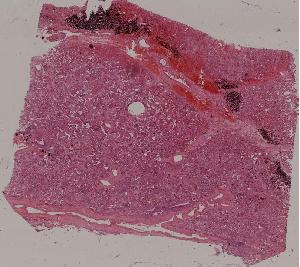

62.急性普通型病毒性肝炎

63.慢性活动性肝炎

64.急性重型病毒性肝炎

65.亚急性重型病毒性肝炎

66.活动性结节性肝硬化

67.非活动性结节性肝硬化

68.胆汁性肝硬化

69.肝细胞性肝癌